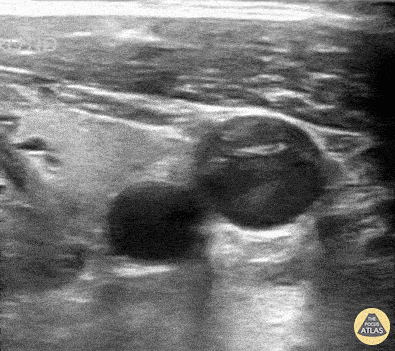

Patient presented with near-syncope and unilateral neck pain. Ipsilateral neck ultrasound revealed swirling blood within the IJ; further evaluation revealed etiology to be a thoracic aortic dissection contributing to pericardial effusion and cardiac tamponade. Peter Weimersheimer, MD. Director EM POCUS at ULA @VTEMSONO